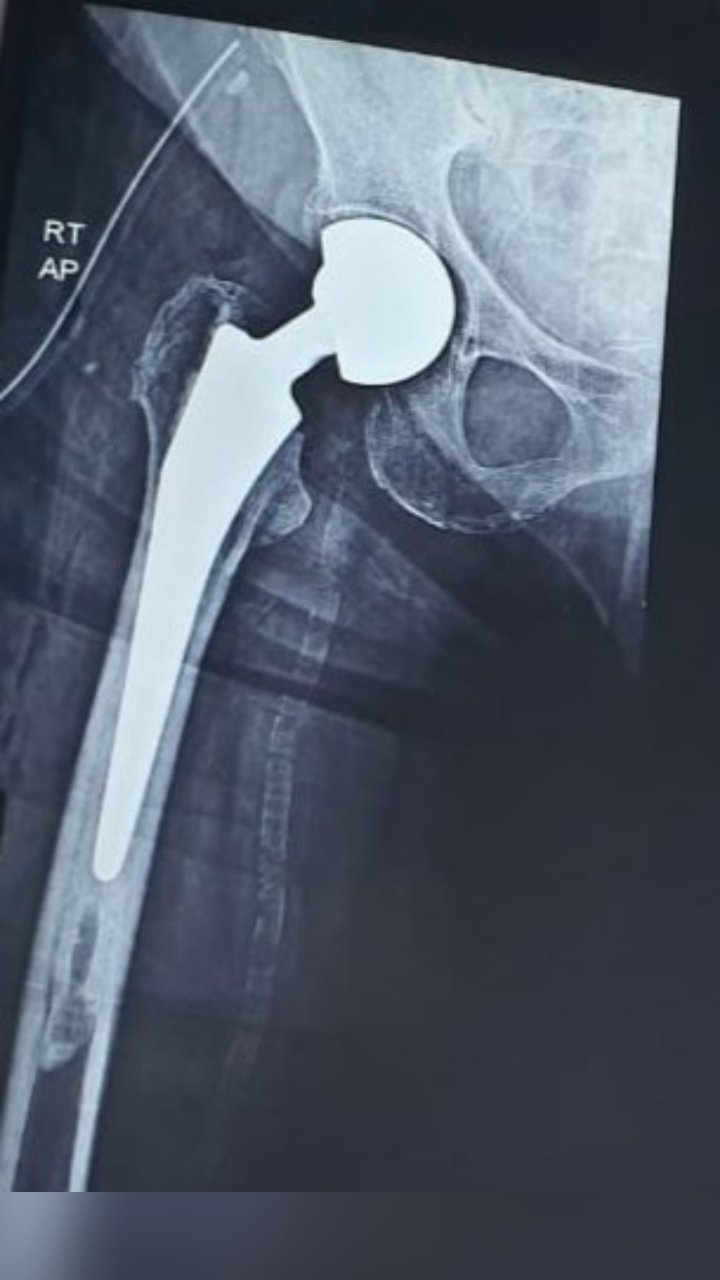

TOTAL HIP REPLACEMENT

BIPOLAR HIP HEMIARTHROPLASTY